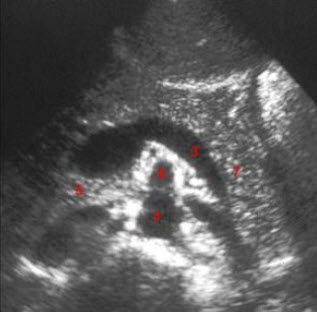

52、单项选择题

女性,29岁,停经28周,产前超声检查如图,最可能的诊断为()

A.胎儿畸形,脑积水

B.胎儿畸形,腹壁裂

C.胎儿畸形,室间隔缺损

D.胎儿畸形,无脑儿

E.胎儿畸形,露脑畸形